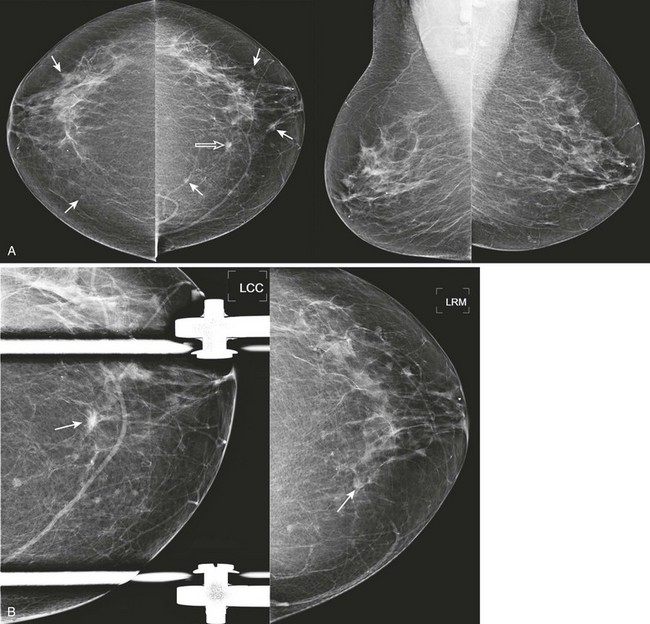

FIGURE 8-6 Multiple Masses with Malignancy.

Screening mammogram of a 40-year-old woman (A). Multiple masses are seen bilaterally (arrows). A right breast mass is dense for its size (open arrow). The patient was recalled and this mass is shown to have spiculated margins on a craniocaudal (CC) spot compression view (open arrow; B, top). US shows a corresponding hypoechoic solid mass with indistinct margins (B, bottom). Two left breast cysts were also seen. Diagnosis: IDC and ductal carcinoma in situ (DCIS) in the right breast.

FIGURE 8-7 Multiple Masses and IDC.

Screening mammogram of a 75-year-old woman shows multiple bilateral less-than-1 cm masses (arrows). A, One mass (open arrow), in the medial left breast, is denser than the others and has spiculated margins. B, The appearance remains suspicious on CC spot and CC rolled medial views (arrows). Diagnosis: infiltrating carcinoma with ductal and lobular features and DCIS.